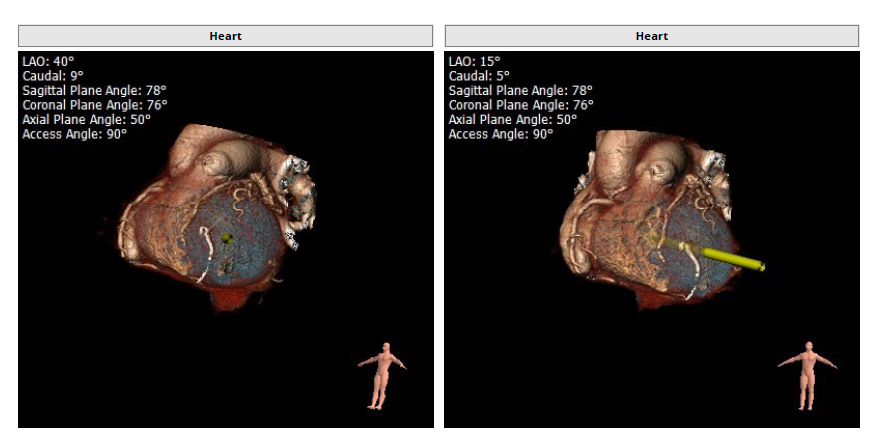

经过安贞医院心外科瓣膜中心王坚刚主任、王盛宇主任,以及胡秋明、郑帅、孟斐、焦玉清、李岳环、沈经纶、吴凯胜等医师团队,以及提交全院心外科质量管理委员会综合讨论评估该患者病情后,患者为重度FMR患者,为传统外科手术极高危患者,决定进行MitraFix®经心尖二尖瓣植入。术前心脏CTA瓣环面积折算最大直径34.5mm 模拟植入29号二尖瓣瓣膜, 心室Neo LVOT面积可。

手术采用左侧第六肋间微创4cm切口心尖入路,在超声引导下,清晰识别MitraFix®输送系统准确跨瓣,并将人工瓣膜准确释放于二尖瓣瓣环,瓣膜释放后支架贴合牢固,术后无反流,二尖瓣前向血流通畅,左心室流出道通畅,流出道血流速度为1.2 m/s. 后顺利撤出输送系统,关闭心尖切口,手术顺利结束,手术skin-to-skin过程仅20分钟。